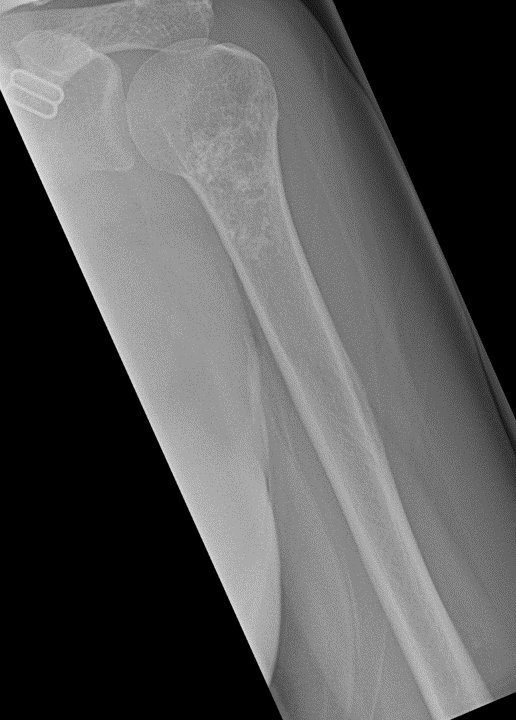

Sie sehen folgendes Röntgenbild. Worum handelt es sich hier?